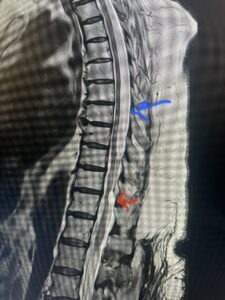

This 67-year-old female presents with progressive heaviness and numbness of the legs and difficulty ambulating. Her right leg was worse than her left. She had right greater than left hip flexor weakness. She was hyperreflexia in her lower extremities. An MRI (Fig. 1) demonstrated an intradural arachnoid cyst at T10-11 with severe spinal cord compression. She also appeared to have an arachnoid cyst above from T4-T8 with anterior displacement and compression of the spinal cord. Because of her severe myelopathy and the findings on MRI the patient underwent laminectomy for surgical decompression of cyst. Intraoperatively the focal arachnoid cyst at T10-11 appeared as a small bubble crushing the spinal cord anteriorly with scarring of the arachnoid with no CSF flow above or below.

The cyst was fenestrated and immediately CSF flow was reestablished. We performed a laminectomy at T6-7 for the upper cyst region which was observed to be more consistent with normal anatomy. We fenestrated the arachnoid. It was felt that the upper level was a secondary phenomenon as a result of CSF flow blockage. Post operatively she had an uneventful course with return of normal strength although she had some residual numbness.

Fig. 1 Sagittal T2-weighted thoracic MRI demonstrating both T10-11 focal intradural arachnoid cyst (red arrow) and larger upper thoracic cyst that appears to extend from T4-T8 (blue arrow).